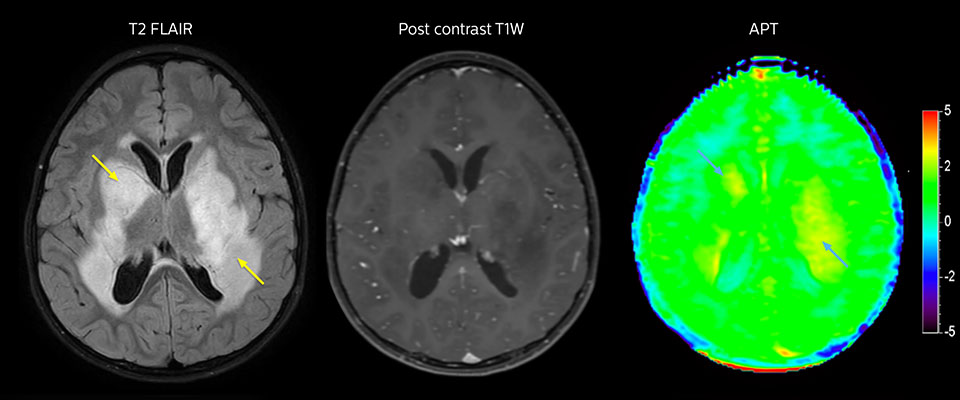

APT in post-surgery evaluation

Large metastatic brain lesion

This 10-year-old patient underwent Ewing’s sarcoma tumor resection 7 years ago, but was found to now have a large metastatic lesion in the brain. This lesion shows clearly increased APT signal.

MRI with APT post resection

Immediately post resection MRI was again performed. T2-weighted and postcontrast T1-weighted images are quite inconclusive for distinguishing residual tumor tissue from postoperative tissue changes. On the APT image some high signal is still seen, which would suggest residual tumor tissue.

Follow-up over time results

Follow-up over time

In later follow-up scans the post-contrast T1-weighted images suggest recurrent tumor growth. So, it would be interesting to study the predictive value of APT in a large patient group.